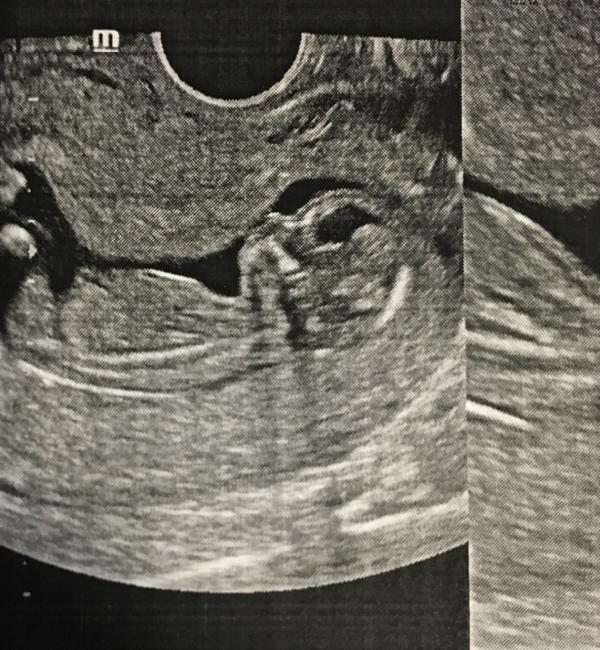

На 14.04 по УЗИ у нас было так:

🎀 Акушерский срок (не точный, по нему не ориентируемся): 14,3 недель.

🎀 Эмбриональный срок: 13 недель.

🎐 Срок на сегодня: 14’1 неделя.

🚼 Пол: неизвестно (я думаю, Азаровская из вредности не сказала, потому что ребёнок лежал так же, как и в первую беременность. В первую беременность под сказали в 12’2 недели.)

📏 КТР: 68 мм.

🤰🏻 Прикрепление: по передней стенке (в 1 беременность было по задней стенке).